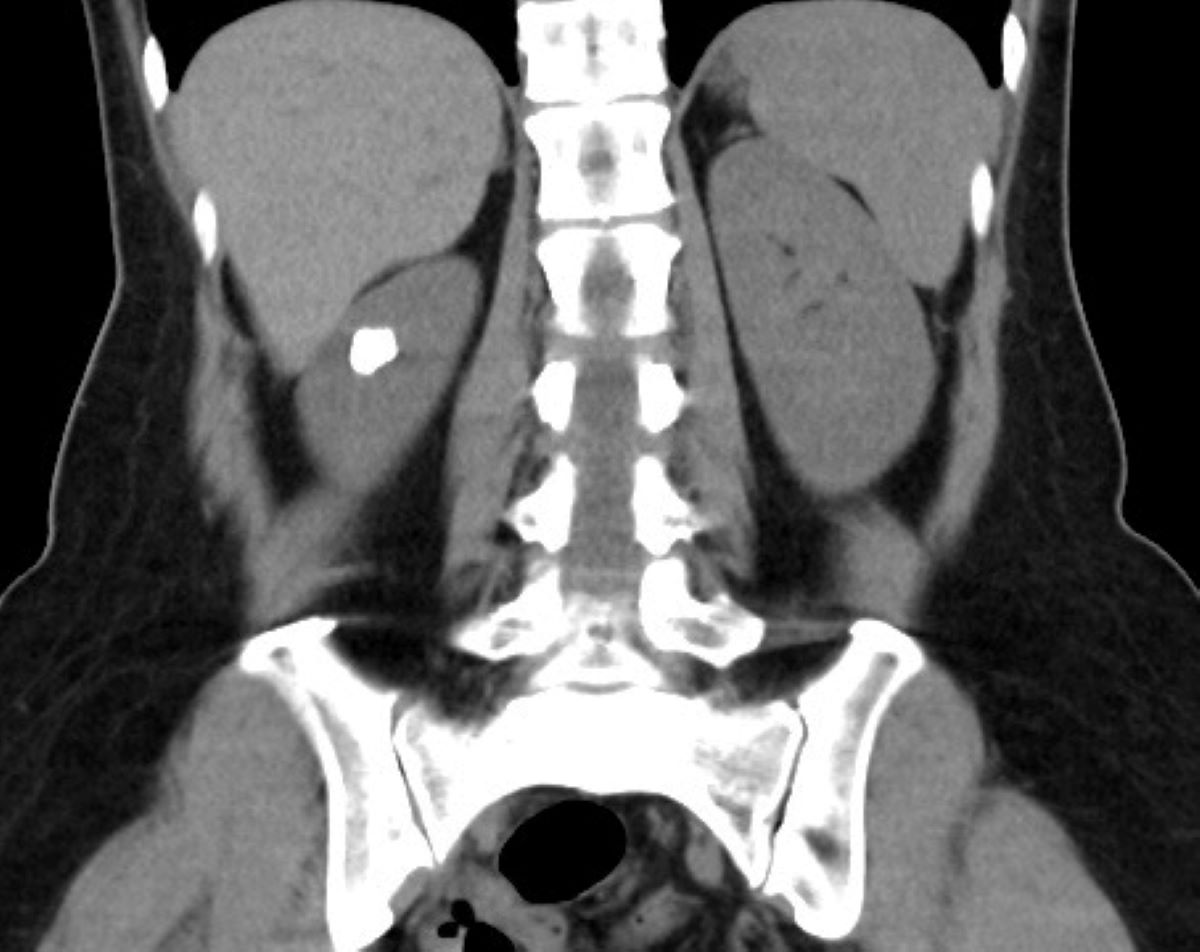

50歲的田女士天生患有腎盞憩室並伴隨結石,但因擔心傳統開刀手術的傷口與復原期,多年來僅在住家附近的診所定期追蹤。直到近期頻繁受到泌尿道感染困擾,嚴重影響生活品質,才轉至台北慈濟醫院就診。泌尿科鐘伯恩醫師經電腦斷層檢查發現,田女士左側腎臟內約有1.5公分的結石群嵌在腎盞憩室中,而憩室與正常腎盞之間的通道僅不到1毫米,導致尿液排出不良並形成結石。手術時先以具止血效果的雷射切開並擴大憩室狹窄的通道,接著以「負壓吸引鞘與軟式輸尿管鏡碎石手術」將結石擊碎並同步吸出,放置雙J導管維持通道通暢直至傷口定型後取出,以降低日後再次狹窄及尿液滯留的風險。術後田女士恢復良好,隔日即順利出院,成功解決多年來的結石與反覆感染問題。

鐘伯恩醫師表示,腎盞憩室是一種較罕見的先天性腎臟結構異常,腎盞向外形成囊袋狀空間,發生率約0.2%至0.6%。由於憩室內尿液排空較差,容易造成尿液滯留並形成結石,部分患者可能出現反覆泌尿道感染、血尿或腰痛等症狀。由於腎盞憩室與正常腎盞之間的通道通常較為狹窄,尿液容易在憩室內滯留,進而增加結石形成的機會。部分患者因此會出現反覆泌尿道感染、血尿或腰部疼痛等症狀。若長期反覆感染未妥善治療,可能造成腎臟功能受損,甚至引發膿瘍或敗血症等嚴重併發症。2025年,鐘伯恩醫師曾於美國醫學會期刊《JAMA Network Open》發表的《腎結石病史與上泌尿道上皮癌生存預後之關聯》論文中提及,泌尿系統結石病史與較高的「上泌尿道尿路上皮癌」發生率有關,且在罹患泌尿系統癌症後存活期顯著較短,癌症死亡風險更比無結石病史者高約83%。因此,儘管腎盞憩室結石初期並未造成明顯不適,仍需盡早就醫檢查,避免拖延錯失治療良機、導致嚴重併發症甚至癌變。